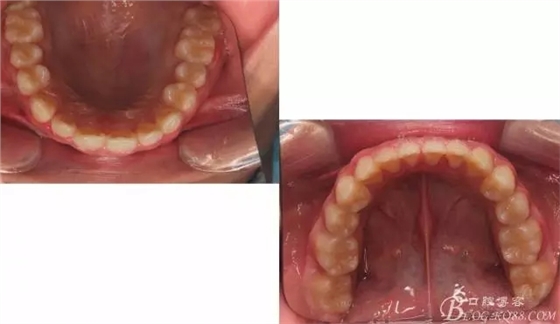

??茩z查:恒牙列,牙列式上下7-7.覆蓋二度,覆合三度,雙側(cè)磨牙關(guān)系二類,尖牙關(guān)系二類,下合3-3各牙間散在約1-1.5mm間隙,輕度唇傾,正面觀顯下頜頦部發(fā)育不足,側(cè)貌可觀察到下頜略顯后縮,上頜鼻唇角以及唇部大體正常。開口型向下,舌體正常,TMJ檢查及其它未發(fā)現(xiàn)異常。

三度深覆合,三度深覆蓋,尖牙,磨牙均二類關(guān)系!